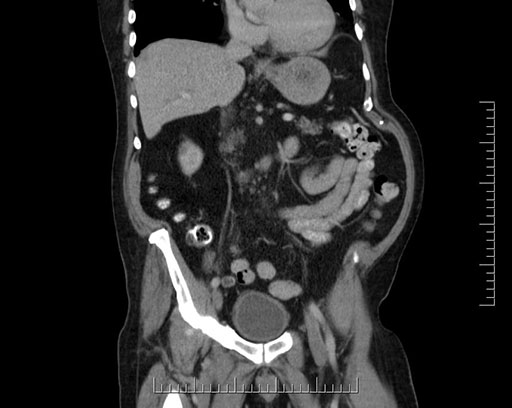

Coronal - stented